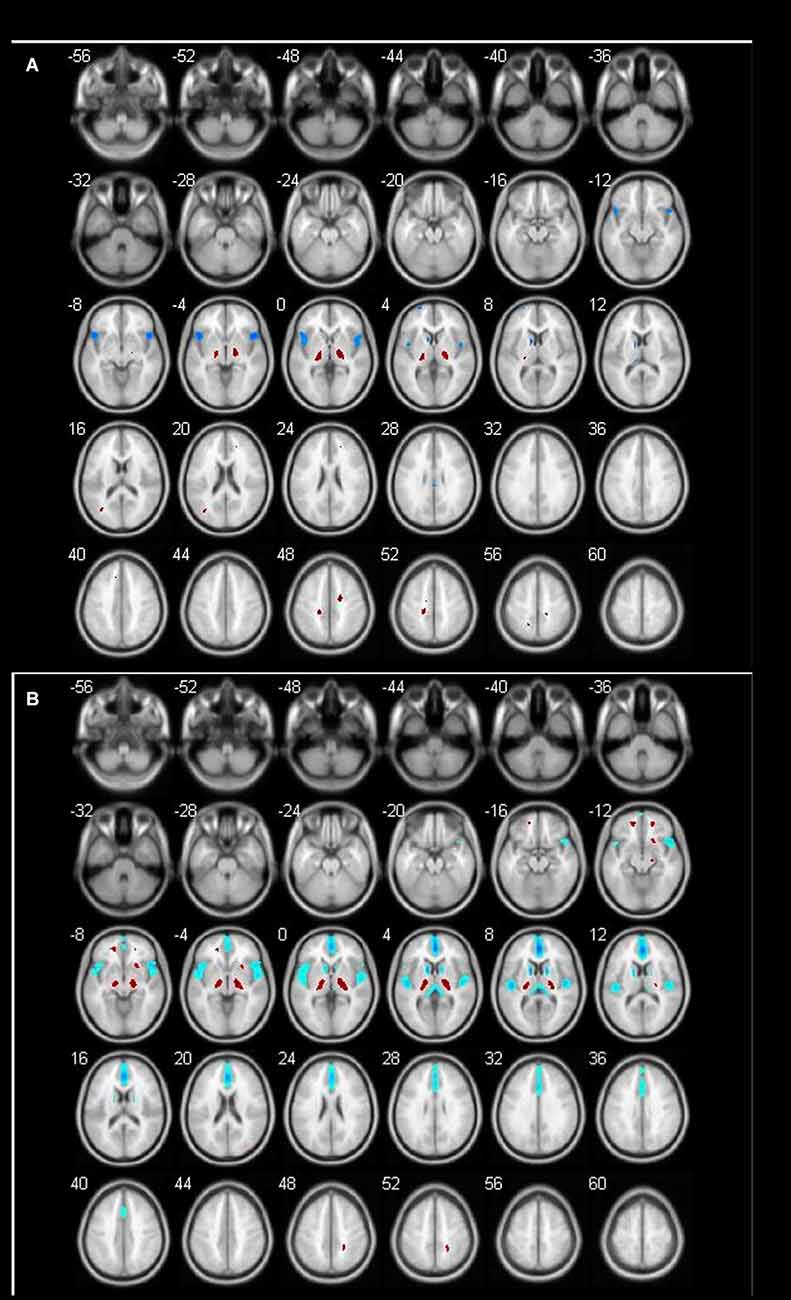

Changing Pattern of Brain Metabolism Over Ages in Different Gender Groups

The age-related glucose metabolism differences between males and females were listed in Tables 4–7 and Figures 2, 3. No decrease or increase metabolic changes were found before the age of 60s in both groups.

Figure 2. Different brain regions in male groups (blue indicates decrease; red indicates increase). (A) Male 60–69 age group; (B) male 70–89 age group.

Figure 3. Different brain regions in female groups (blue indicates decrease; red indicates increase). (A) Female 60–69 age group; (B) female 70–89 age group.